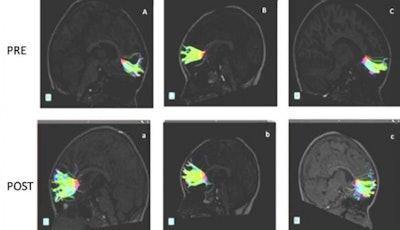

DTI-MRI scans were performed before and after the lessons to look for microstructural changes in the brain's white matter, which contains millions of nerve fibers called axons that connect various regions of the brain. More specifically, DTI measures the movement of extracellular water molecules along axons through fractional anisotropy. High fractional anisotropy values indicate a normal, uniform flow of these molecules in healthy white matter, while lower values indicate a more random movement of the water molecules and suggest abnormalities.

The DTI scans revealed an increase in fractional anisotropy and axon fiber length in different areas of the brain, most notably in the minor forceps, which are located in the frontal cortex.